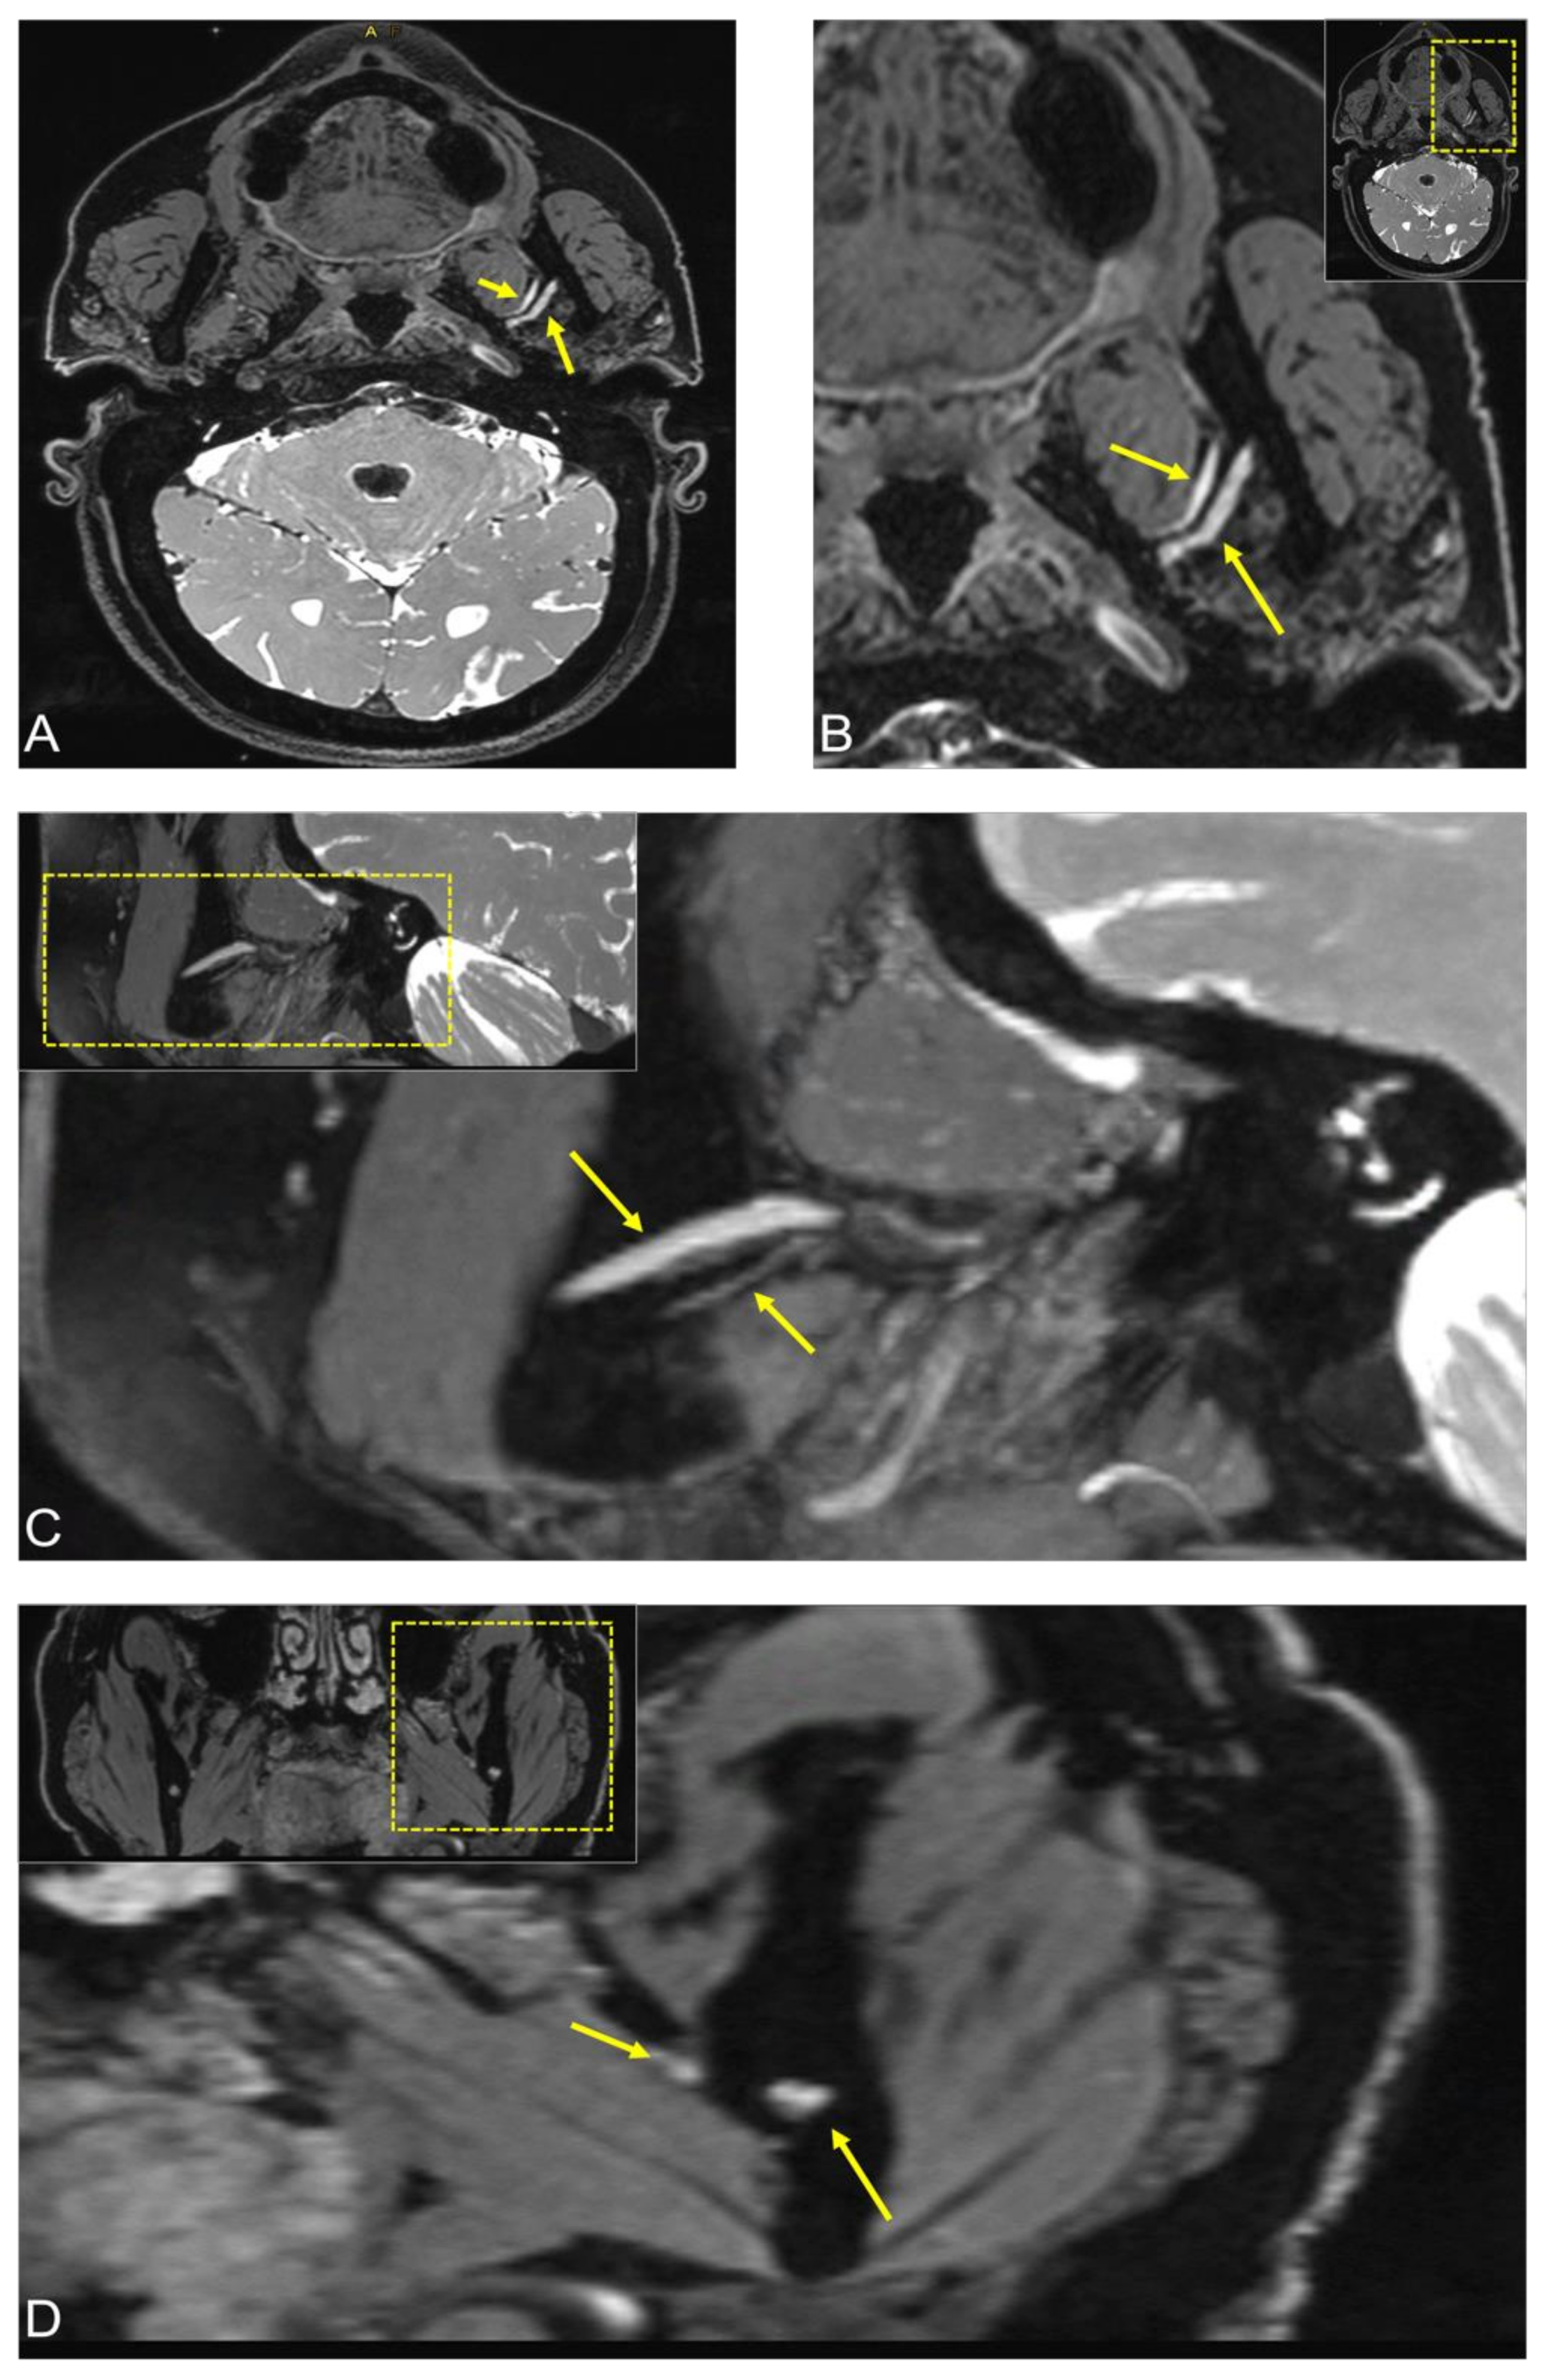

2.1. Case 1